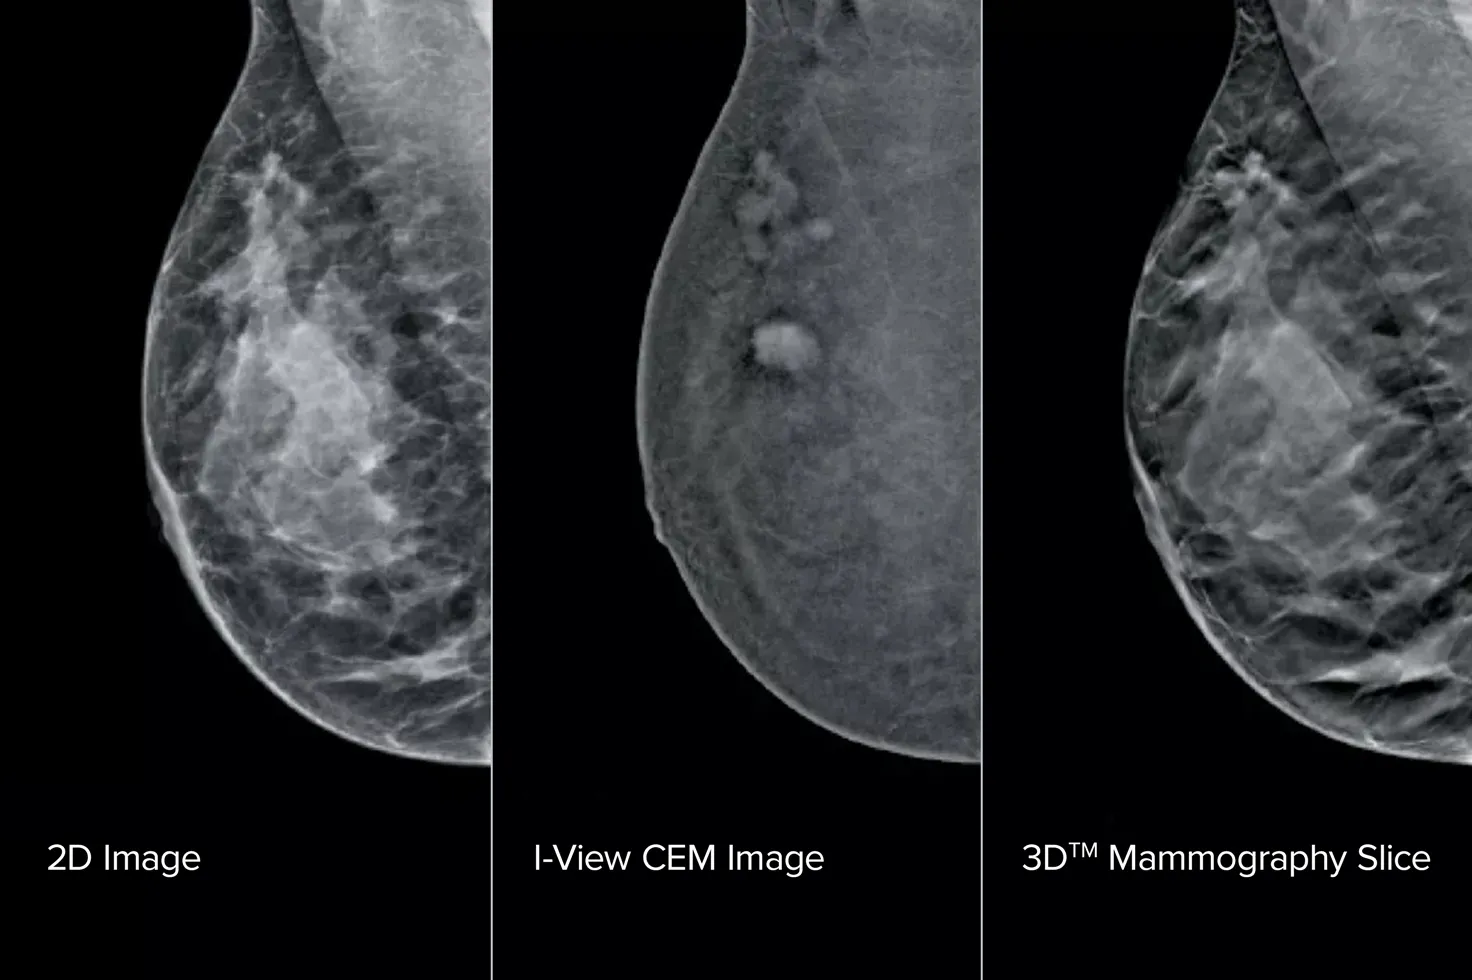

Contrastversterkte mammografie (Contrast Enhanced Mammography; CEM), het in beeld brengen van de borst met gebruik van jodiumhoudend contrastmiddel om gebieden met een verhoogde bloedtoevoer in de borst zichtbaar te maken, kan helpen om het beeld van verdachte laesies te versterken. De I-View-software kan de kracht van CEM combineren met 2D- en tomosynthesebeelden, allemaal bij één compressie, voor anatomische en functionele beeldvorming in één onderzoek.1

Deze software legt zowel anatomische als functionele informatie vast bij één onderzoek door gebruik te maken van ons vermogen om 2D-, contrast- en tomosynthesebeelden te produceren bij slechts één compressie.1